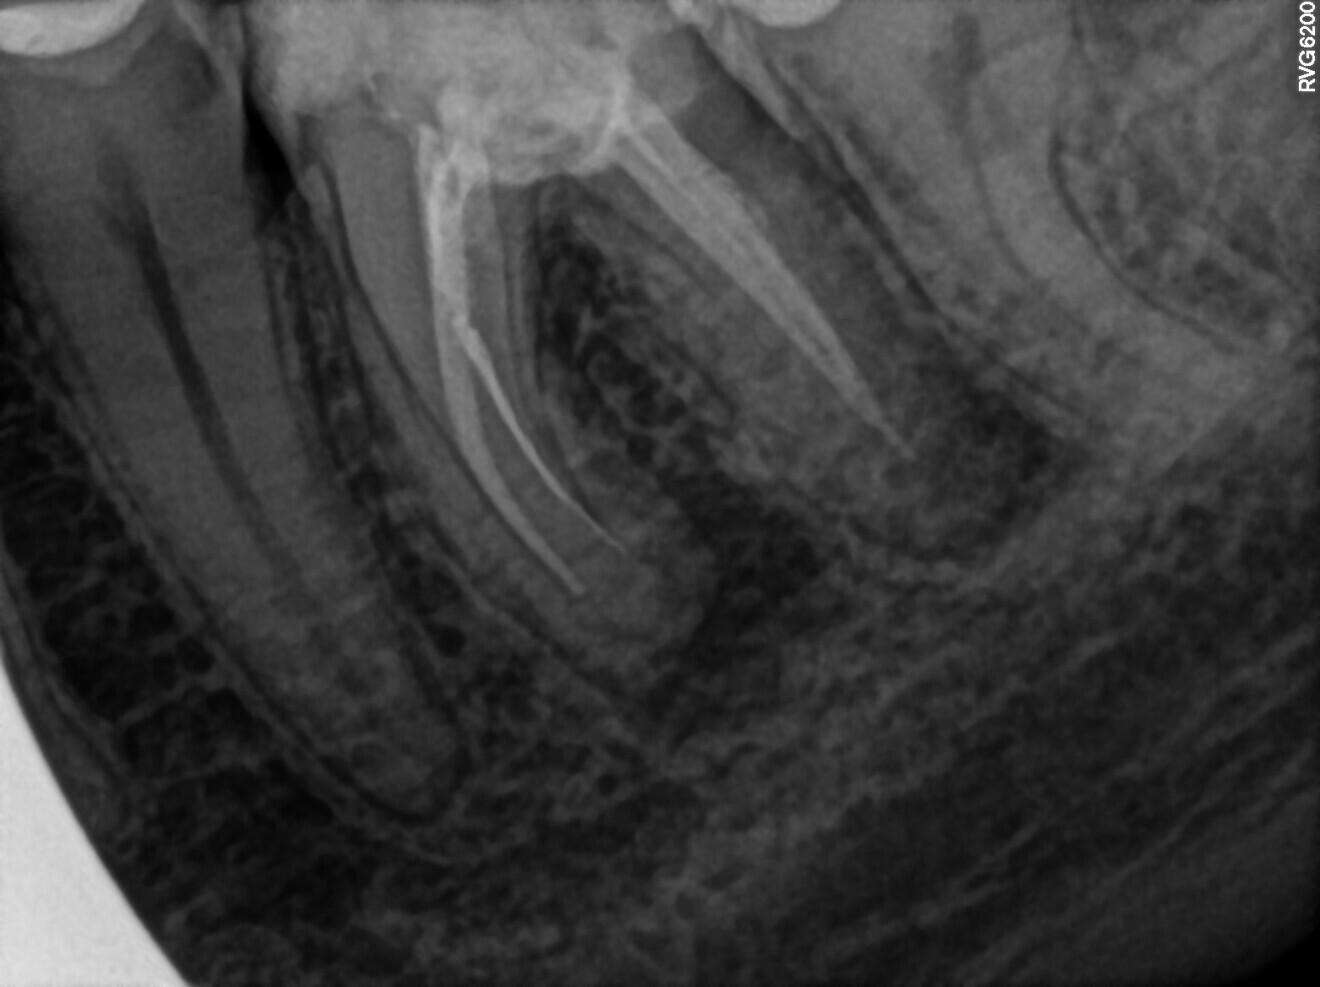

Fig. 1: Pre-op radiograph. Periapical lesion and broken file visible.

The periapical radiograph and the CBCT scan revealed that the file had broken far beyond the curvature in the mesiobuccal canal and below the junction with the mesiolingual canal. Also, a periapical lesion was visible around the apices of the mesial and distal roots (Figs. 1–3). The length of the file was approximately 5 mm. Bypassing the file through the mesiolingual canal would have been a risky procedure because it may have caused the fracture of the second instrument and the obturation may also have been very challenging. Thanks to SWEEPS technology and a bioceramic sealer, an alternative approach could be taken. After administering anaesthesia and placing a dental dam, the temporary restoration was removed (Figs. 4 & 5). The pulp chamber was rinsed with 5.25% sodium hypochlorite and the irrigant activated with ultrasonics. After cleaning the chamber of the tooth, the dental dam and clamp were rinsed with water and dried and flowable dental dam was placed to seal the tooth and enlarge the space in the pulp chamber for the laser-activated irrigation (Fig. 6). Activation was performed with the SkyPulse laser (Fotona). The AutoSWEEPS mode was chosen. The power of activation was set to 1 W. The flat SWEEPS 300/20 fibre tip was used (Fig. 7). The tip was placed slightly below the orifice of the mesiobuccal canal for the majority of the irrigation with sodium hypochlorite. After 120 seconds of activation with sodium hypochlorite, the tip was placed in the pulp chamber to activate the sodium hypochlorite in all the canals simultaneously for 30 seconds. This procedure was continued for 30 minutes. Only the distal canal was shaped with rotary files, up to size 40/.04. Both mesial canals remained the same size as they were before the file broke during the primary treatment. Finally, the canals were flushed with EDTA activated with AutoSWEEPS at a power of 0.4 W, and sodium hypochlorite was activated for three cycles with AutoSWEEPS at a power of 0.6 W and with a 30-second break for the resting phase. The irrigant flow between the mesiobuccal and mesiolingual canals was rapid, indicating that obturation could be performed.